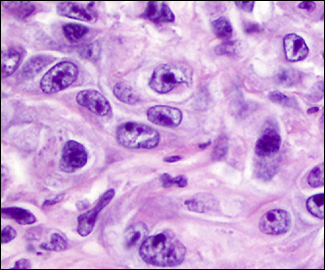

术后病理:多发性平滑肌瘤,部分富于细胞,生长活跃,可见核异型、橘红色核仁、嗜酸性小球及鹿角状血管,偶见核分裂象,免疫组化FH(-)。

FH缺陷型子宫肌瘤多发于年轻女性,其病理形态学表现为肿瘤细胞具有不典型性,可出现明显的嗜酸性橘红色大核仁、核周空晕、嗜酸性胞质内小球及鹿角状血管,核分裂象偶见。FH缺陷型子宫平滑肌瘤具有特征性的形态学表现,肿瘤细胞具有不典型性,常提示富于细胞,生长活跃,易过诊断为恶性潜能未定的平滑肌肿瘤或平滑肌肉瘤,免疫组化染色示肿瘤细胞FH表达缺失可协助诊断。术后病理提示FH缺陷型平滑肌瘤后,建议密切随访患者,并进一步行分子检测。因FH基因胚系突变具有遗传性,故临床中需注意提醒患者在生育前行遗传咨询,必要时考虑辅助生育或产前诊断,尽可能避免遗传给后代的可能,同时加强肾细胞癌相关筛查。